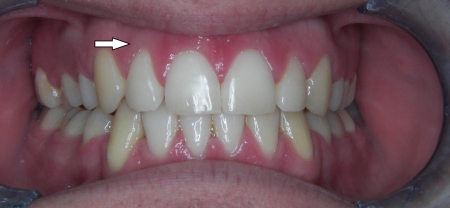

Kompresija –fiksni aparat i ekstrakcija jednog donjeg sjekutića

U sljedećem primjeru prikazan je pacijent s kompresijom koji je već bio u ortodontskoj terapiji. Za rješavanje kompresije donje čeljusti izvađen je sjekutić. Nkon terapije je došlo i do smanjenja recesija na očnjacima jer smo pomakli zubni korijen u bolji položaj.